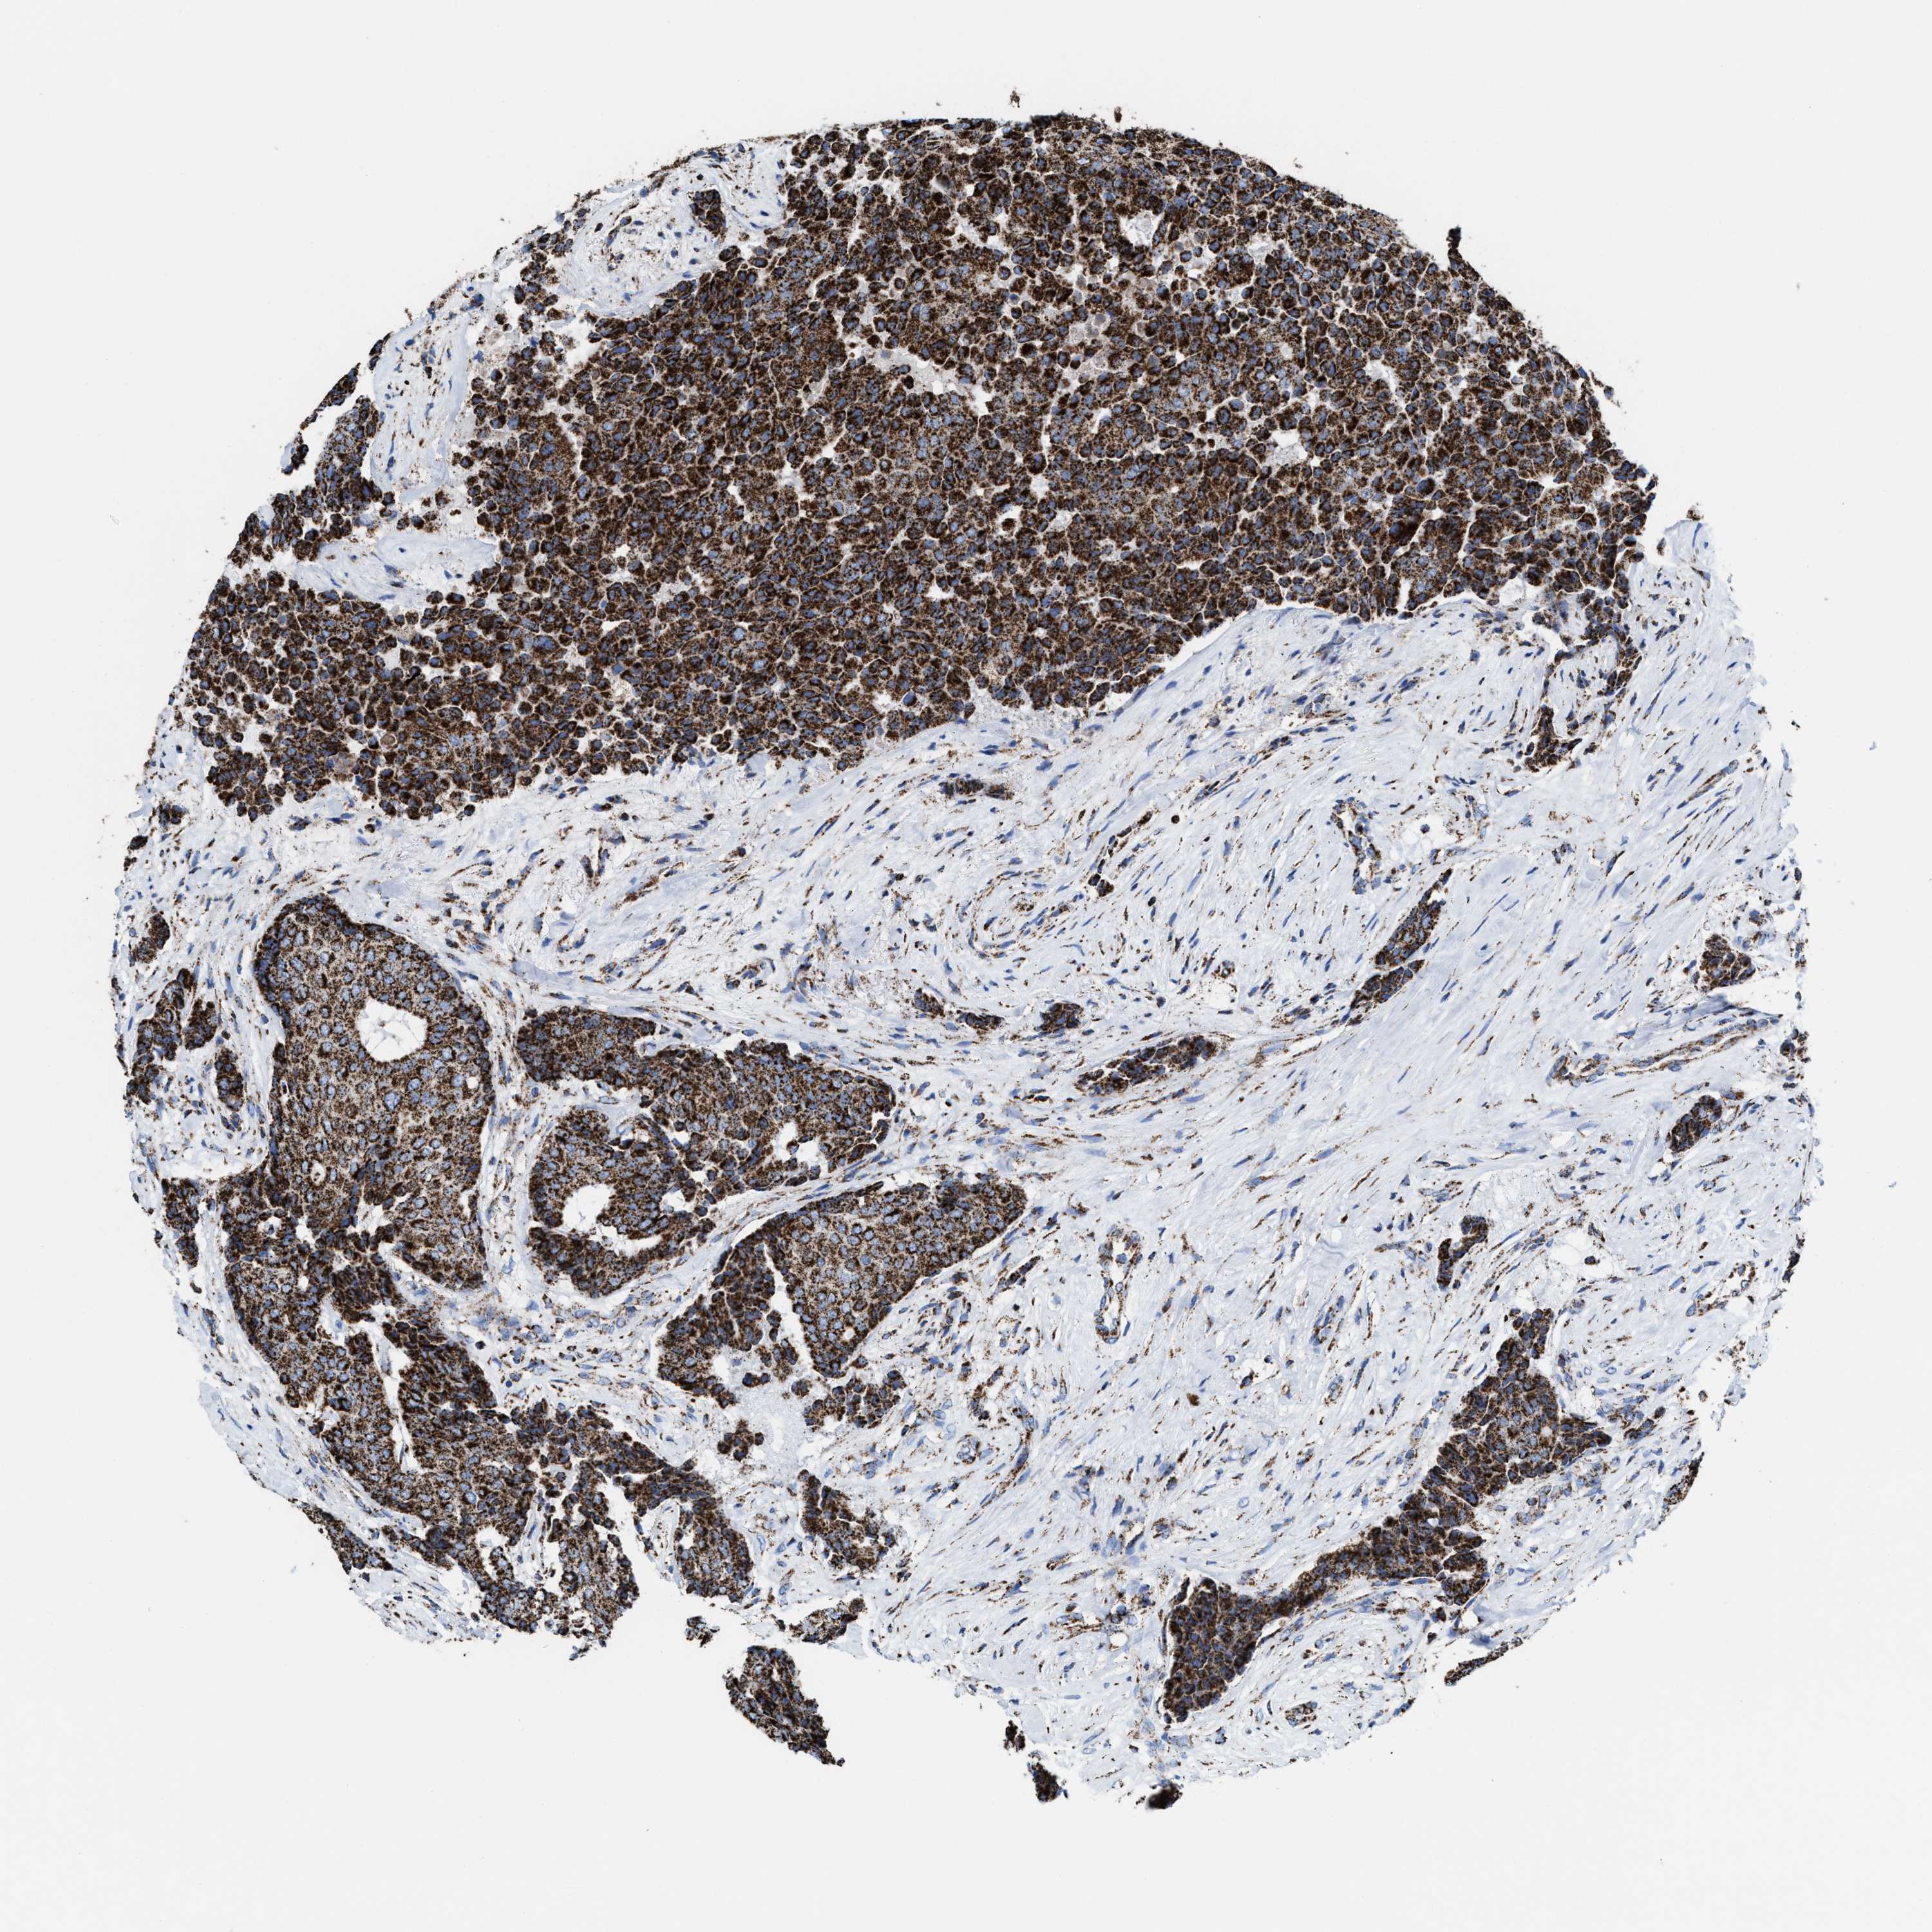

CANCER BREAST CANCER Show tissue menu

BRCA TCGA BRCA VALIDATION PROTEIN EXPRESSION

ANTIBODIES

AND

VALIDATION